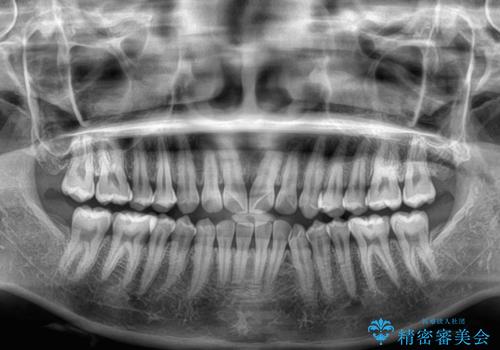

- 上下前歯のデコボコを気にして来院された患者様です。

ワイヤー矯正でもマウスピース矯正でも可能でしたが、短期間で、自身の手を煩わせることなく治療を行いたいとのことで、ワイヤー装置にて矯正治療を行うこととしました。